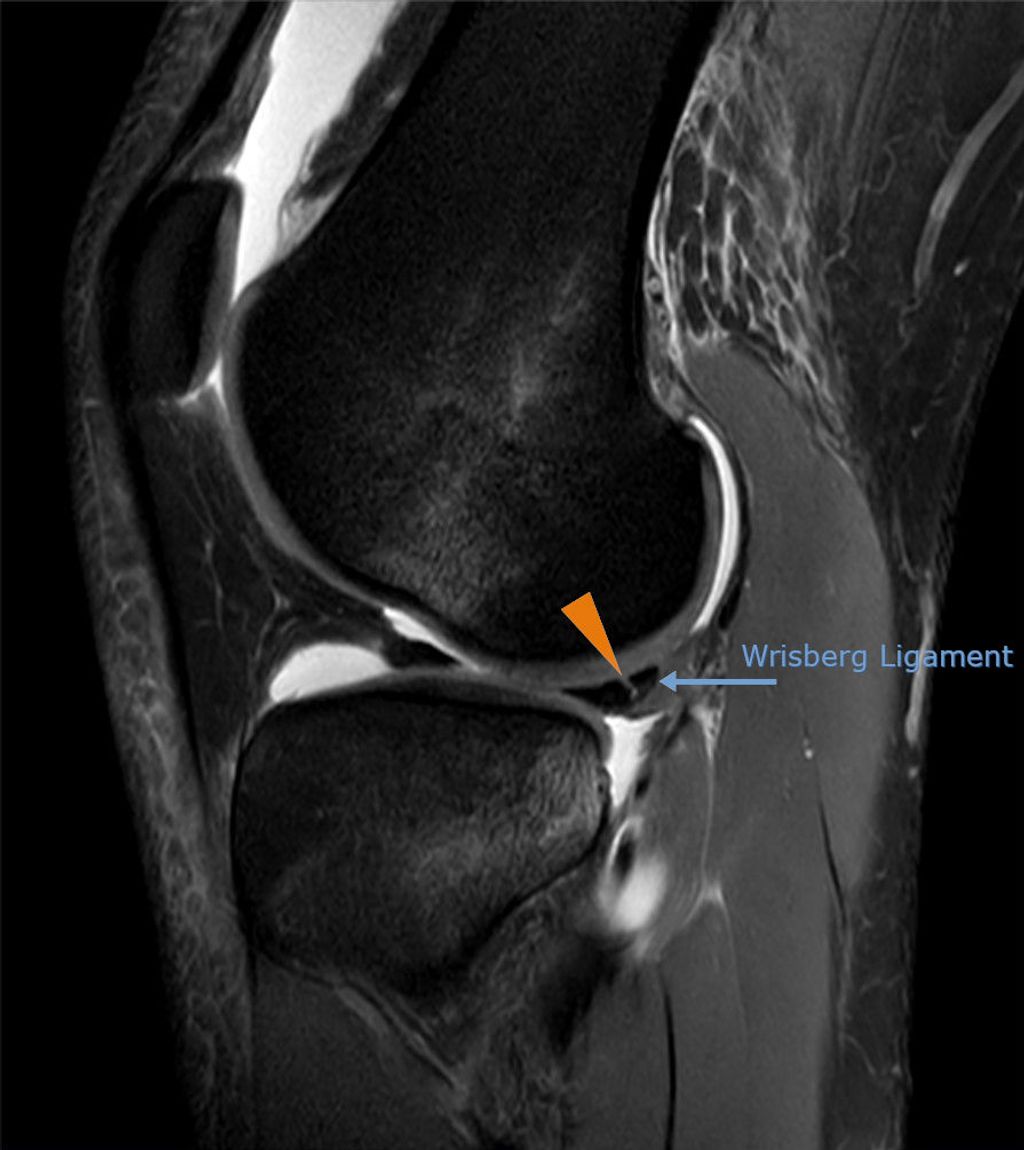

Imaging Techniques

In our quest to accurately diagnose meniscus injuries, we often turn to imaging techniques. These methods provide us with a clear picture of the internal structures of the knee, allowing us to assess the extent of the injury. Magnetic Resonance Imaging (MRI) is the gold standard for visualizing meniscus tears due to its high sensitivity and specificity. However, we also consider other modalities such as ultrasound and X-rays, particularly when MRI is contraindicated or unavailable.

Ultrasound is advantageous for its real-time imaging capabilities, which can be particularly useful in dynamic assessments. X-rays, while not as detailed for soft tissue injuries, can help rule out other conditions such as fractures or osteoarthritis. It’s important to note that while imaging provides valuable information, it should be interpreted in conjunction with clinical findings.

Tip: Always correlate imaging results with physical examination findings to ensure a comprehensive assessment of the meniscus injury.